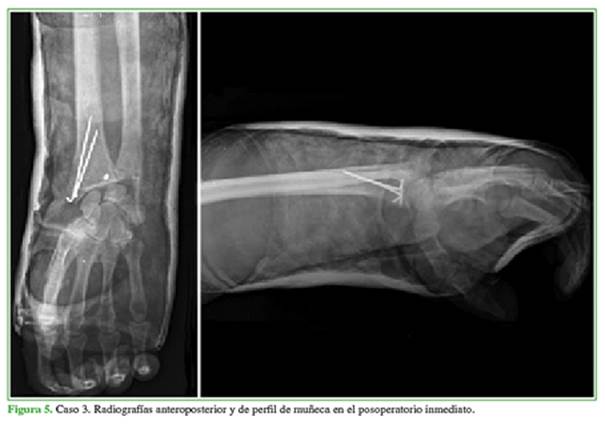

Los controles se realizaron a los 15, 30, 90, 180 y 345 días con radiografías anteroposteriores y de perfil de muñeca (Figuras 5 y 6). Desde el punto de vista objetivo clínico/funcional, se evaluaron los rangos de movilidad en flexión, extensión, pronosupinación y las desviaciones cubital y radial, tomando como parámetro normal de referencia el miembro contralateral sano en una escala del 0% al 100%.

Con relación a la técnica quirúrgica, en su gran mayoría, este tipo de lesiones requiere de una osteosíntesis de la estiloides radial, reanclado de la cápsula articular y sutura ligamentaria (radiosemilunar corto). Se utilizó el abordaje de Henry para radio distal (Figura 3). No fueron necesarios abordajes dorsales debido a la correcta reducción indirecta de los fragmentos fracturarios. La estabilidad/reducción fue controlada mediante radioscopia dinámica en el quirófano (Figura 4).